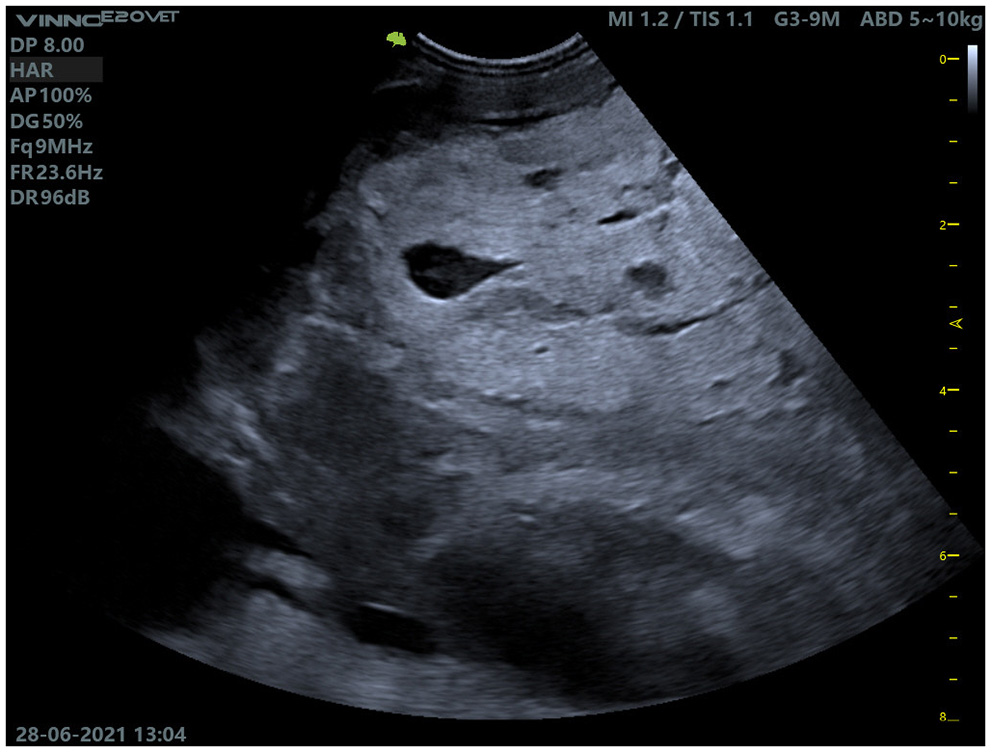

During the clinical examination in the clinic, the goat was apathetic in sternal recumbency and was unable to keep its head up independently. The animal tried to stand up several times, but repeatedly collapsed. The animal was in a severely emaciated state, the protuberances of the spine and ribs were easily palpable. Bodyweight was 59.5 kg, rectal temperature 39.2°C. The conjunctival mucous membranes were white [FAMACHA©-score of 5 (32, 33)], indicating severe anemia. The episcleral vessels were slightly filled. Auscultation of the heart revealed tachycardia (heart rate of 144 beats/min). The heart sounds were regular but poorly separated, there were no secondary murmurs. Auscultation of the lungs revealed a weak inspiratory sound over the entire lung field and tachypnea (respiratory rate of 96/min). The goat's rumen was filled and fluctuating, two contractions of the rumen could be auscultated in 2 min in the left paralumbar fossa. In the right paralumbar fossa, an intra-abdominal slightly movable solid mass of about 15 cm was palpable. Palpation of the lymph nodes (Lnn. mandibulares, Lnn. parotidei, Lnn. retropharyngei, Lnn. cervicalis superficiales, Lnn. subiliaci) did not reveal any deviations from the norm. The skin of the goat was dry and scaly without macroscopic evidence of ectoparasites. The udder of the animal was asymmetrical, the left half of the udder was slightly larger than the right half of the udder and of coarse consistency, no secrete could be milked. Palpation of the limbs did not reveal any abnormalities. The mass in the right paralumbar fossa was further examined by ultrasound, it was well-demarcated against the liver, the major part was hyperechogenic with single anechogenic cavities (Figure 1).

Figure 1

Ultrasound examination of the mass in the right paralumbar fossa. The mass was demarcated to the liver (not shown in the picture) and contained individual cavities.